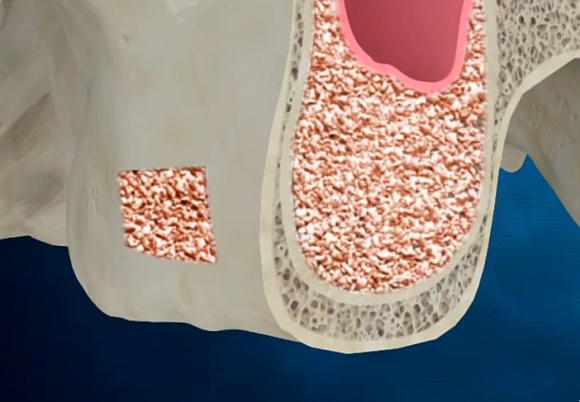

발치한 부위는 예상대로 뼈가 매우 얇아져 있어, 안정적인 인공치아 식립을 위해 뼈이식과 상악동 거상술을 병행했습니다.

잇몸뼈가 부족하거나 얇은 경우, 임플란트를 단단히 고정하기 위해 인공 뼈를 이식하는 과정을 말하는데요.

상악동 위치를 바꾸고 이공뼈 이식

안정적으로 이식된 인공뼈